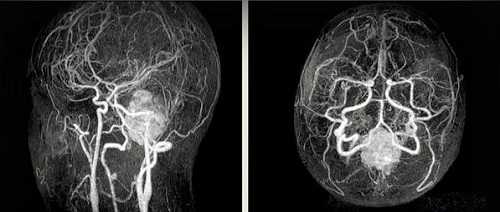

Артерио-венозная мальформация (стрелка)

Сканирование с болюсным усилением проводят в два этапа: после серии нативных снимков делают инъекцию раствора гадолиния. Препарат заполняет кровеносное русло и межклеточное пространство, визуализируя изменения каналов и окружающих тканей.

Контрастная МРТ артерий головного мозга показывает новообразования сосудов и церебральных структур на начальных стадиях формирования. На снимках определяются опухоли диаметром от 3 мм.

Злокачественные образования медленнее накапливают и отдают контраст. Очаги, состоящие из атипичных клеток, обеспечивают гипоинтенсивный сигнал в начале сканирования, по мере увеличения концентрации хелатов гадолиния приобретают яркую окраску.